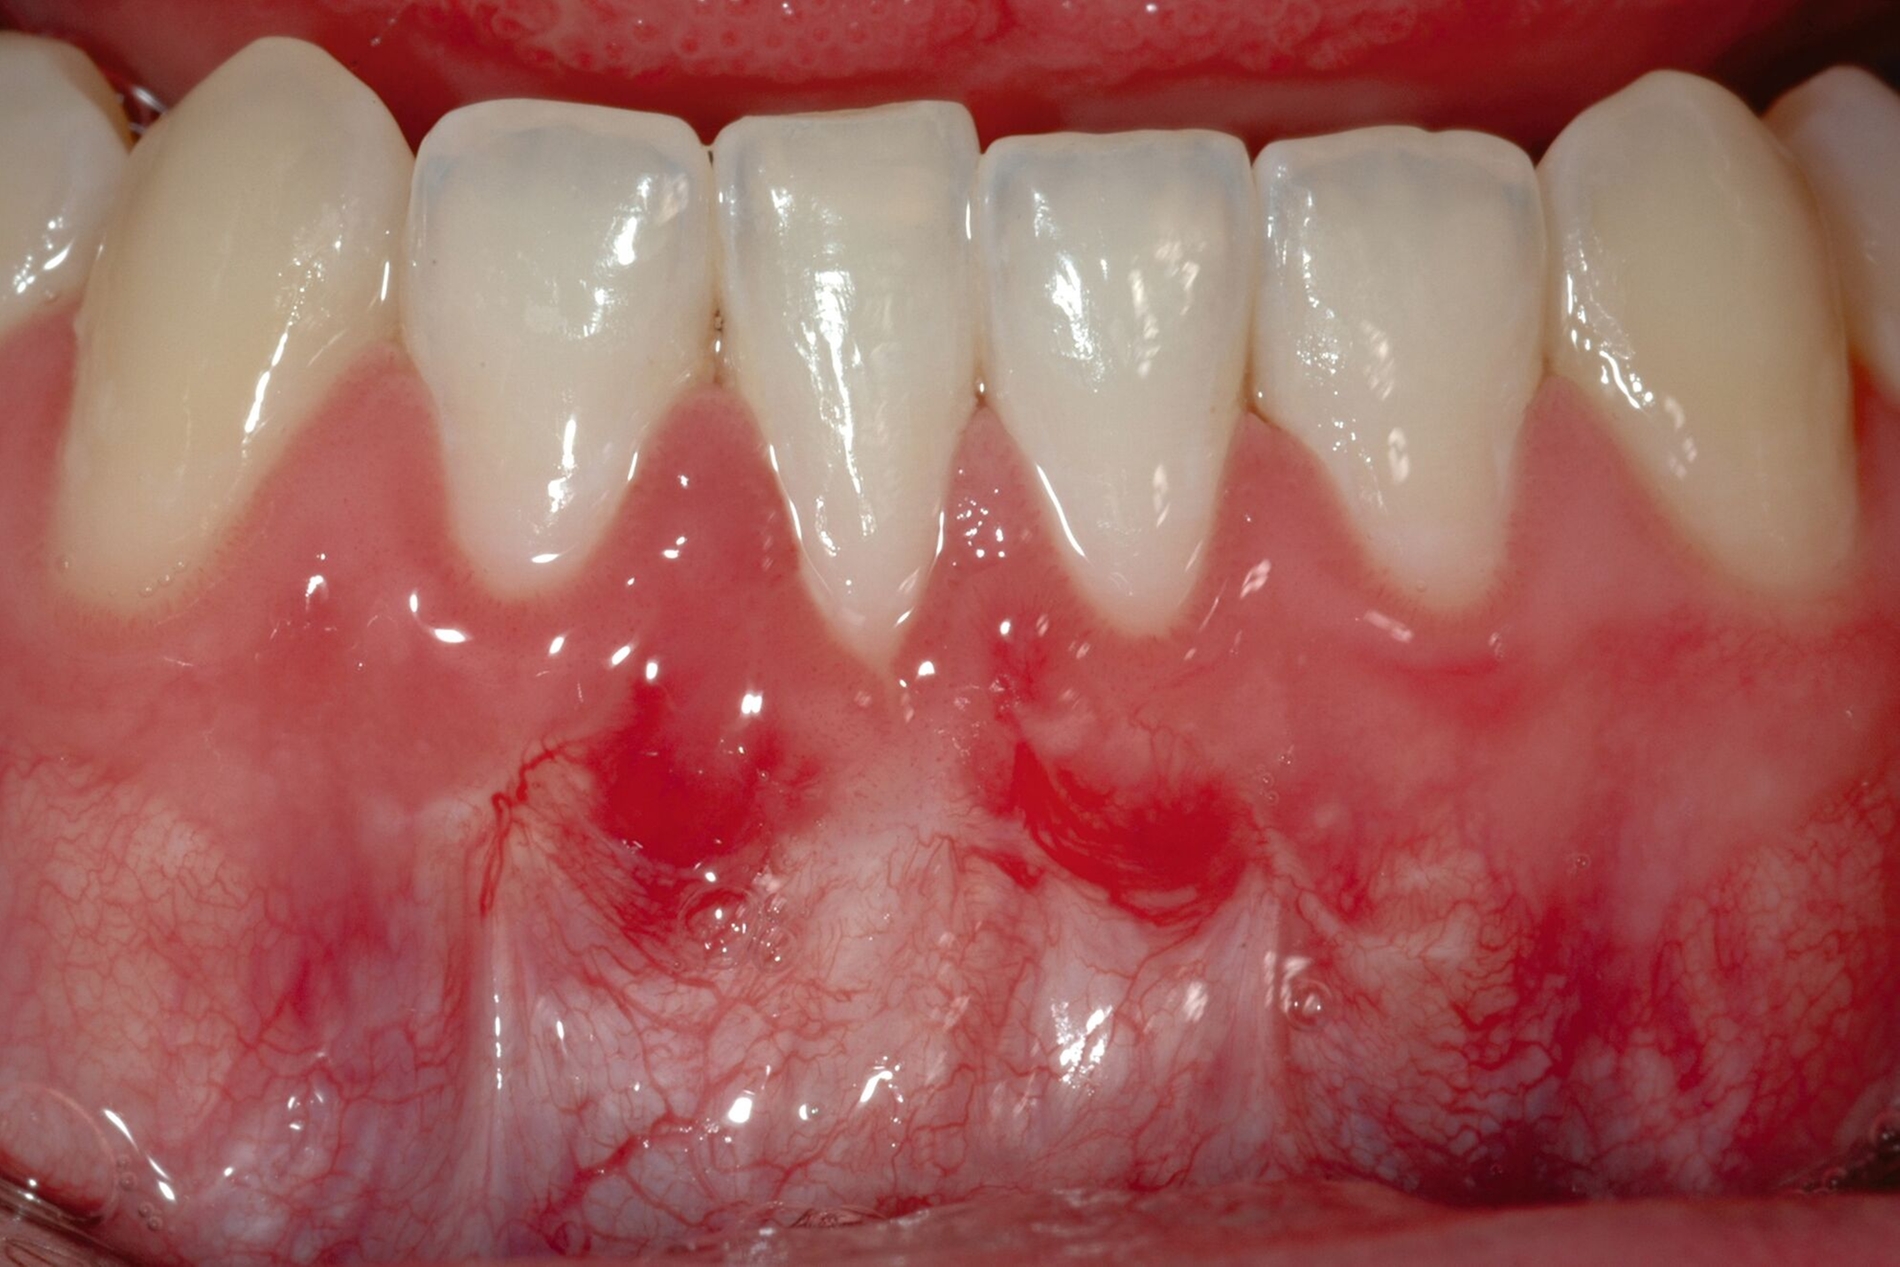

Der Lateral Geschlossene Koronal Verschobene Lappen ermöglicht eine annähernd narbenfreie Deckung singulärer parodontaler Rezessionen durch Verzicht auf vertikale Entlastungsinzisionen (Abbildung 3g). Das Lösen der Papillen im Rahmen der Verschiebung ermöglicht eine deutliche Anhebung des Lappens und somit durch großzügige Überdeckung das Erreichen vollständiger Wurzeldeckungen. Durch den lateralen Verschluss im Rahmen der tiefen, über die mukogingivale Grenze hinausgehenden Rezession kann keratinisierte Gingiva im Bereich dieser hergestellt und eine übermäßige Mobilisation und damit Einschränkung des Vestibulums verhindert werden.

Weiterer Bekanntheit erfreut sich der Lateral Geschlossene Tunnel (LCAT) nach Sculean & Allen [Sculean und Allen, 2018; Sculean et al., 2021]. Diese Methode zeigt durch das fast völlige Ausbleiben postoperativer Vernarbungen einen deutlichen Vorteil gegenüber den oben genannten Verfahren. Allerdings weisen Patienten nach Tunneltechniken verglichen mit Verschiebelappen tendenziell eine größere postoperative Morbidität auf. Nachteil der Tunneltechniken ist zudem die eingeschränkte koronale Verschiebbarkeit, die mit einer geringeren Quote mittlerer und vollständiger Wurzeldeckungen einhergeht [Pini Prato et al., 2005; Salhi et al., 2014; Santamaria et al., 2017; Neves et al., 2020]. An dieser Stelle setzt der Lateral Geschlossene Koronal Verschobene Lappen (LCAF) nach Tunkel an [Tunkel et al., 2024]. Anders als beim LCAT werden hier auch die Papillen vom interdentalen Col gelöst, so dass ein wirklicher Verschiebelappen gebildet wird. Dies ermöglicht eine Überdeckung der Schmelz-Zement-Grenze von mehr als 2 mm, so dass die vollständige Wurzeldeckung vorhersagbarer erreicht werden kann. Die vorübergehende sichtbare Lappen-Grenzlinie im Bereich der Papillen ist nach drei bis zwölf Monaten in der Regel ohne weitere Maßnahmen annähernd vollständig verschwunden, so dass auch hier ein Ergebnis visueller Narbenfreiheit erwartet werden kann. Ansonsten ist das Funktionsprinzip des LCAF vergleichbar mit dem LCAT. Im Gegensatz zum LCAT existieren vom LCAF allerdings noch keine klinischen Fallstudien, Fall-Kontroll-Studien oder gar randomisierte, kontrollierte klinische Studien, so dass die wissenschaftliche Evaluation dieser Methode noch abgewartet werden muss.